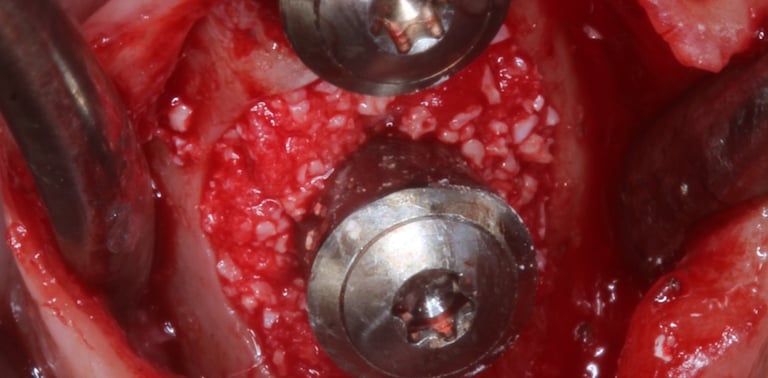

Le traitement chirurgical de la péri-implantite constitue aujourd’hui un enjeu majeur en implantologie pour assurer la pérennité des traitements et la satisfaction des patients.

Cette formation DPC, interactive et clinique, vous permettra de maîtriser les protocoles chirurgicaux les plus récents pour contrôler l’infection et stabiliser les tissus péri-implantaires. À travers des situations réalistes et des analyses radiographiques, vous serez guidé pas à pas pour transposer les recommandations scientifiques dans votre pratique quotidienne.

Connaître et appliquer les différentes approches chirurgicales (résectrices, régénératrices et combinées).